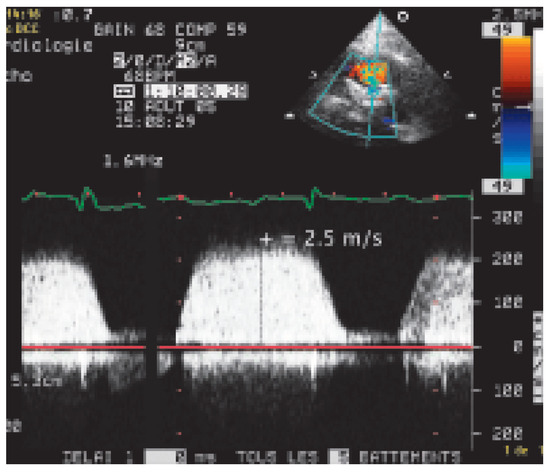

Palpitations Anciennes, Malaises Récents

by Jürg Schläpfer

Cardiovasc. Med. 2006, 9(4), 166; https://doi.org/10.4414/cvm.2006.01164 - 28 Apr 2006

Histoire clinique. Patiente de 55 ans ayant présenté des épisodes de palpitations dans l’adolescence sans documentation ECG et qui, après un intervalle libre de plus de 20 ans, se plaint de malaises fréquents [...] Full article